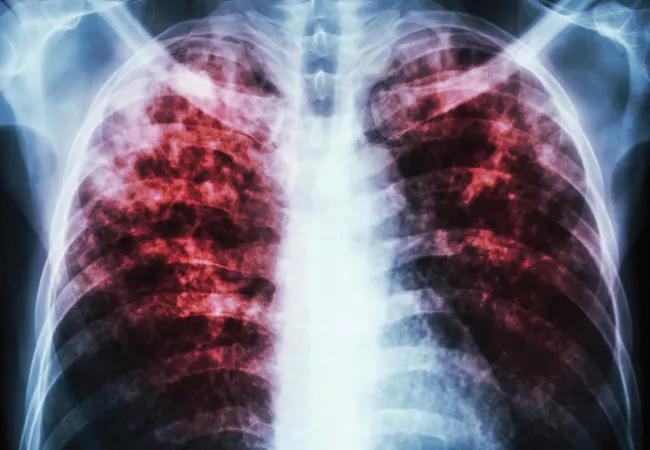

Tips for Keeping Cystic Fibrosis Patients Out of the Hospital During the COVID-19 Pandemic

Managing CF at home is possible, but steps must be taken by both patient and caregiver

Although COVID-19 poses a major risk to all patients, those with cystic fibrosis (CF) may be at a particularly high risk of death should they be hospitalized with COVID-19, according to expert opinion. Appearing in Cleveland Clinic Journal of Medicine’s collection of COVID-19 Curbside Consults, a commentary from Elliot Dasenbrook, MD outlines best care practices for this patient population in the midst of the pandemic.